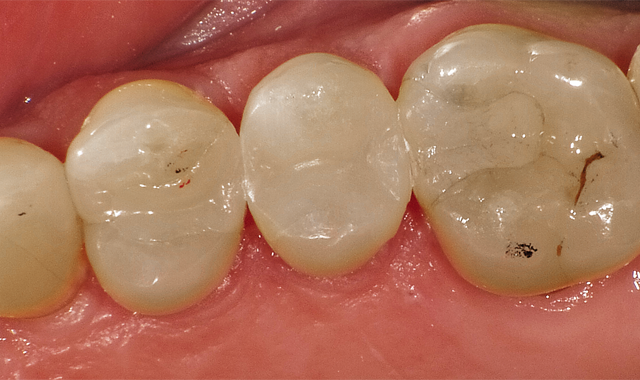

The challenge: Easy to onlay, easier to crown, far more of a challenge to place a direct restoration (Fig. 1).

In Case 1, it was a challenge to place a direct restoration.